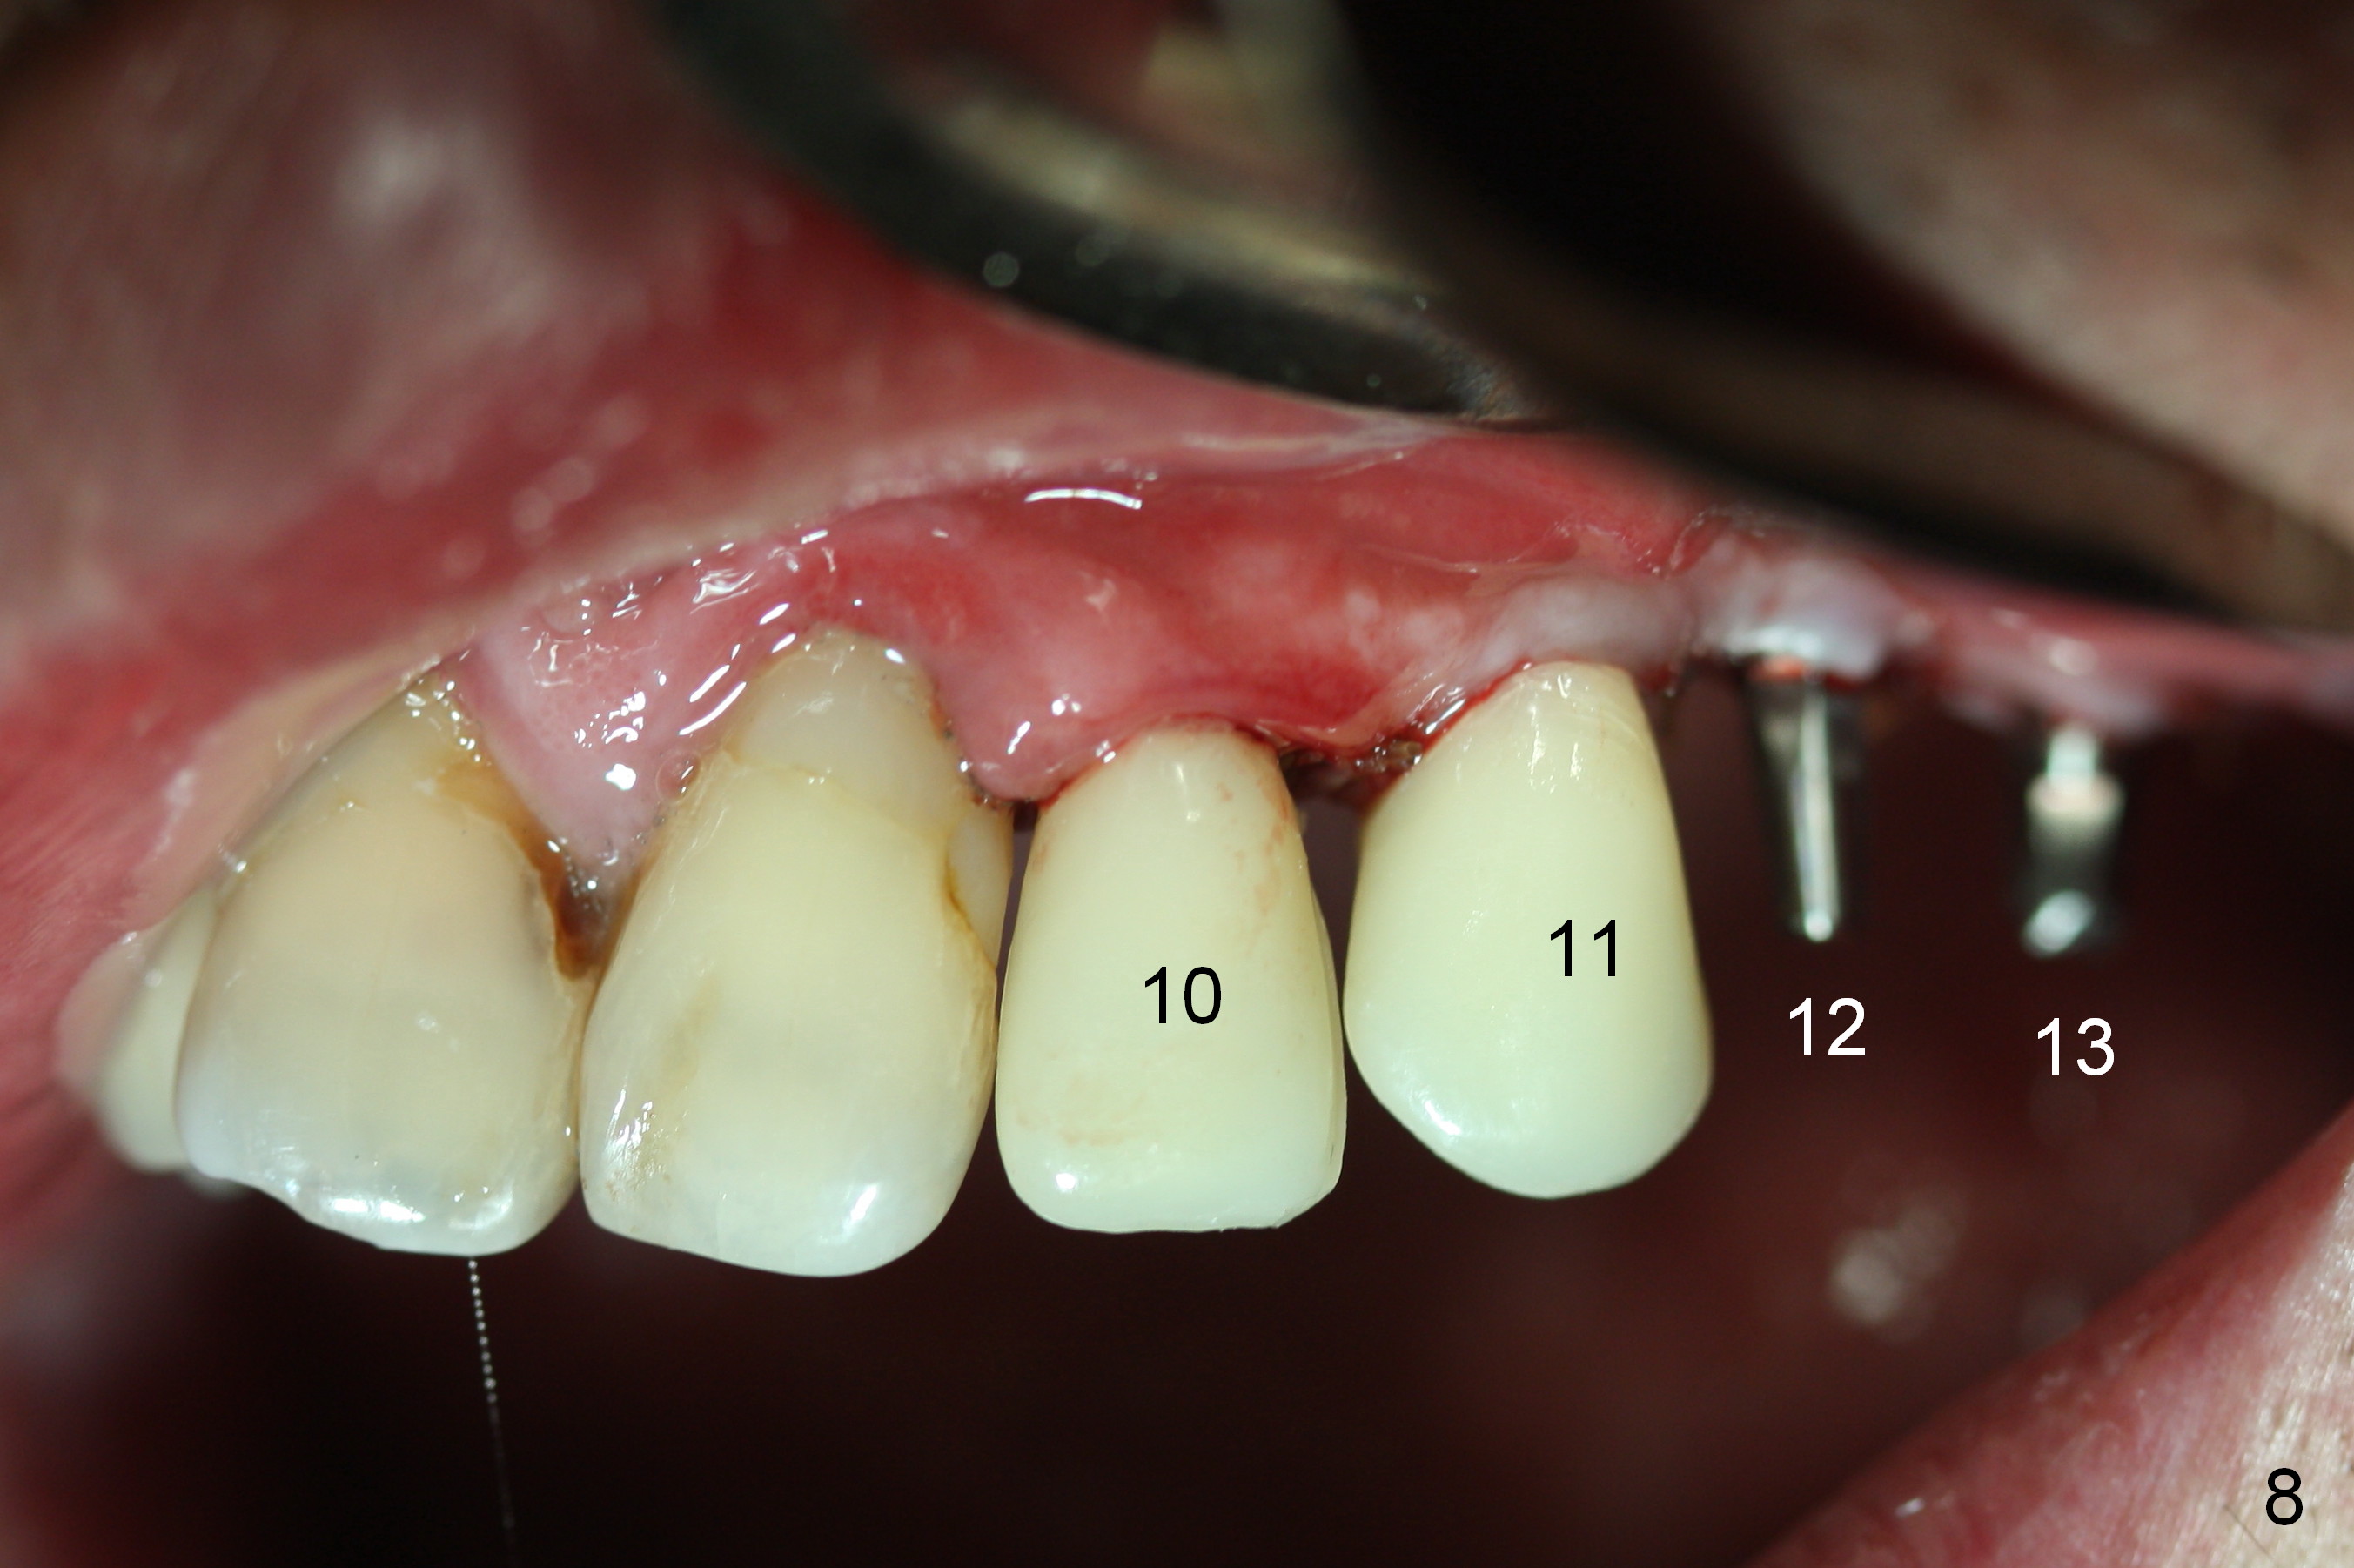

When the patient returns for implant placement (2nd visit after initial exam), he reveals that he is a dental phobic.  He requests placement of 4 implants in the upper left quadrant, instead of 2.  Narrow ridge is unexpected in the canine and premolar area (Fig.1).  Limited bone height at #13 (Fig.3 arrowheads: sinus floor) is found when initial drills are in place (Fig.2,3).  A 2-piece implant (4.5x17 mm tissue-level) is placed at #10 after extraction, while 1-piece implants are placed at 11 (3x17 mm (tissue-level, 15 °) and 12 and 13 (bone-level, 2.5x14, 12 mm, respectively; Fig.4,5).  In fact the 1 piece implant at #13 is not completely placed (Fig.5).  It is removed, the apical 3 threads are cut off (Fig.6 <, since a shorter implant was unavailable in the office) and the remaining implant is re-inserted.  The insertion torques of the 4 implants are ~ 60, ~ 35, < 35 and 15 Ncm, respectively.  After adjustment (Fig.7), immediate provisionals are fabricated at #10 and 11 (Fig.8, later splinted with composite), while perio dressing is applied around the implants at #12 and 13 and the provisionals at #10 and 11.  There is no nasal hemorrhage postop.  Although the perio dressing is loose 1 week postop (Fig.9), it is not removed.  When the upper lip fissure (Fig.9 <) heals, provisionals at #12 and 13 are planned to be splinted to the other two ones.  Two weeks postop, the upper lip fissure heals, the perio dressing dislodges and the implants at #12 and 13 are stable (Fig.10).  After abutment height adjustment, a splinted provisional is fabricated over these 2.5 mm 1-piece implants (Fig.11).